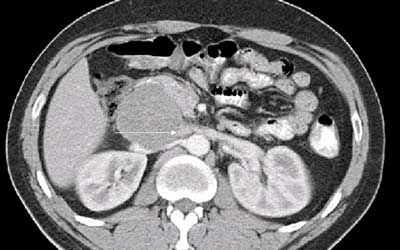

При осмотре в брюшной полости пальпируется подвижное безболезненное и относительно плотное образование. Данные лабораторных анализов — без отклонений, опухолевые маркеры в пределах нормы. Рентгенография брюшной полости показала нормальное распределение газов в кишечнике. Ультразвуковое исследование выявило анэхогенное кистозное образование, занимающее полностью переднюю и правую часть брюшной полости. Каких‑либо патологических изменений кишечника, а также свободной и локализованной жидкости в брюшной полости не обнаружено. КТ брюшной полости и МРТ выявили образование больших размеров — 35×20×10 см, располагавшееся в брюшной полости и полости малого таза, не связанное с какими‑либо органами (рисунок 1).

Во время срединной лапаротомии обнаружена гигантская киста, устье которой было связано с брыжейкой поперечной ободочной кишки (рисунок 2). Образование полностью удалено, органы брюшной полости не пострадали. Макроскопически киста брюшной полости однокамерная, содержит около 5000 мл серозной жидкости. Гистологический анализ показал, что это была простая мезотелиальная киста, фиброзная стенка которой выстлана мезотелиальными клетками правильной формы без атипии и митозов (рисунок 3). Послеоперационный период прошел без осложнений — все показатели пациентки оставались в норме, и она была выписана на следующий день. Шесть месяцев спустя самочувствие пациентки оставалось хорошим, рецидива не было.

Обзорная рентгенограмма и контрастная рентгенография с барием часто дают нормальные результаты или показывают наличие какого‑то образования, смещающего кишечник [6, 9]. УЗИ брюшной полости, КТ и МРТ более информативны [7, 10]. Они могут показать кистозный характер образования, его размеры, расположение и связь с прилежащими органами, а также характер содержимого и стенок кисты [2, 6].

При УЗИ кисте брюшной полости выглядит как анэхогенное образование с акустическим усилением [6, 7, 9]. КТ и МРТ выявляют образование, наполненное жидкостью, с сигналом слабой интенсивности на Т-взвешенных изображениях, без различимых стенок и внутренних перегородок [7, 9]. Данные лабораторных исследований — неспецифичны. Обычно дополнительные диагностические мероприятия (тонкоигольная аспирационная биопсия с цитологическим анализом или обзорная лапароскопия) не проводятся [2].